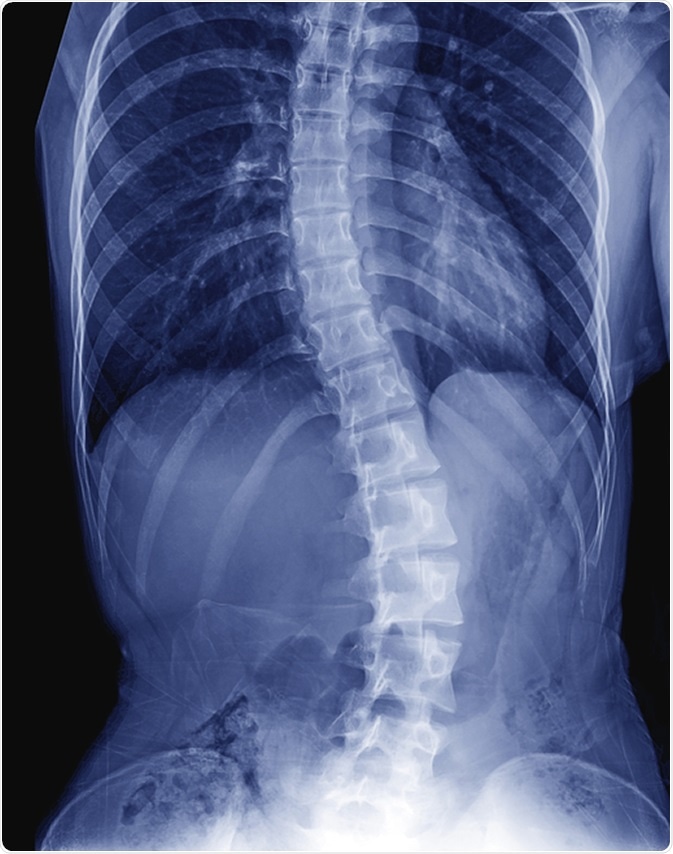

X-ray image of child patient spine show Scoliosis. Image Credit: ChooChin / Shutterstock